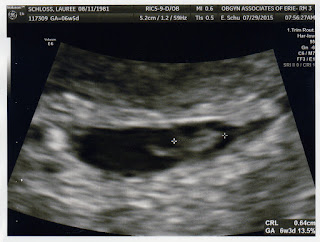

God is good! God is AWESOME! Praise Jesus! We have a heartbeat! 122bm! Baby Schloss measured 6w3d, exactly 7 days more than 7 days ago! Thank you everyone so so so so so much for your thoughts and prayers! We are just so happy words can't explain.

| Heartbeat visualized! 122 BPM! |

| Side view. |

| I think this is his/her spine. Measuring 6w3d. |

| Another measurement: 6w3d. |

| Baby!!! |